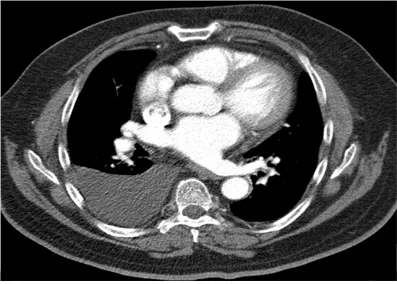

78세 여성이 3일 전부터 숨을 들이쉴 때 생기는 오른쪽 가슴 통증으로 내원하였다. 2주 전부터 기침과 가래가 있었으며, 최근에는 발열과 오한이 동반되었다. 혈압 130/80 mmHg, 맥박 88회/분, 호흡수 24회/분, 체온 38.4℃로 측정되었다. 가슴 청진 시 오른쪽 호흡음이 누그러졌다. 혈액검사와 가슴막삼출액검사 결과, 그리고 흉부 CT를 참고하여 세프트리악손과 클린다마이신 치료를 시작하였다. 다음 중 적절한 처치는 무엇인가?

Rt. pleural effusion

• 발열과 오한을 동반한 호흡기 증상, 오른쪽 호흡음 감소, CT 상 관찰되는 우측 흉수 등으로 흉막 삼출을 의심할 수 있으며, 부폐렴성이 의심된다.